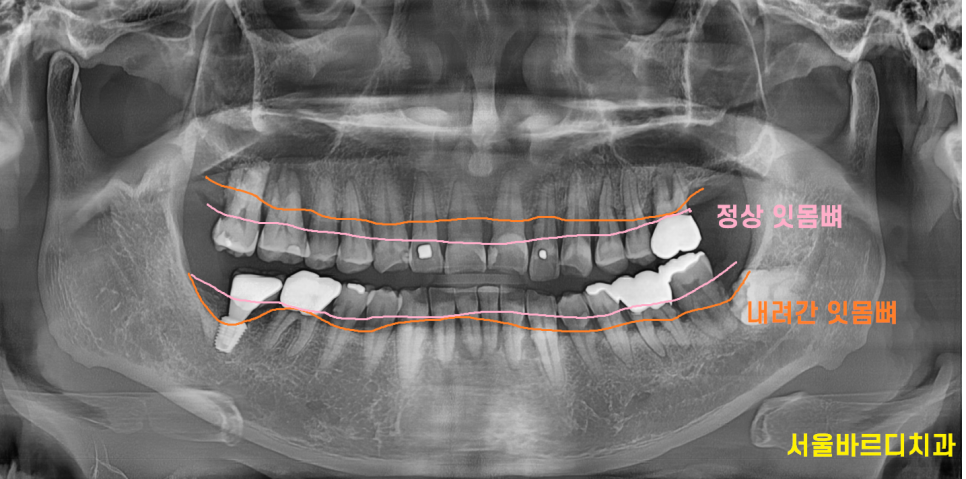

잇몸 무너짐은 잇몸뼈가 내려가는 현상을 뜻합니다.

잇몸이 치아를 제대로 지탱하지 못하고 내려앉는것이죠.

치주질환으로 인해 발생하며 잇몸이 내려가면서

치아가 흔들리는 현상으로 이어질 수 있습니다 .